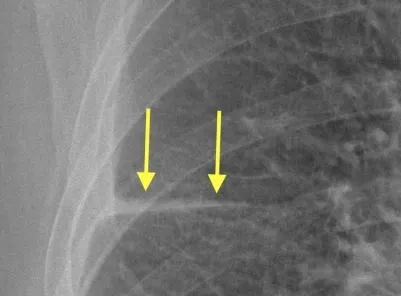

Peribronchial cuffing (doughnut sign): Increased density around the walls of a bronchus or large bronchiole seen end-on, both on plain radiographs and on CT.

<p><b>Peribronchial cuffing</b> (doughnut sign)<b>:</b> Increased density around the walls of a bronchus or large bronchiole seen end-on, both on plain radiographs and on CT.</p>